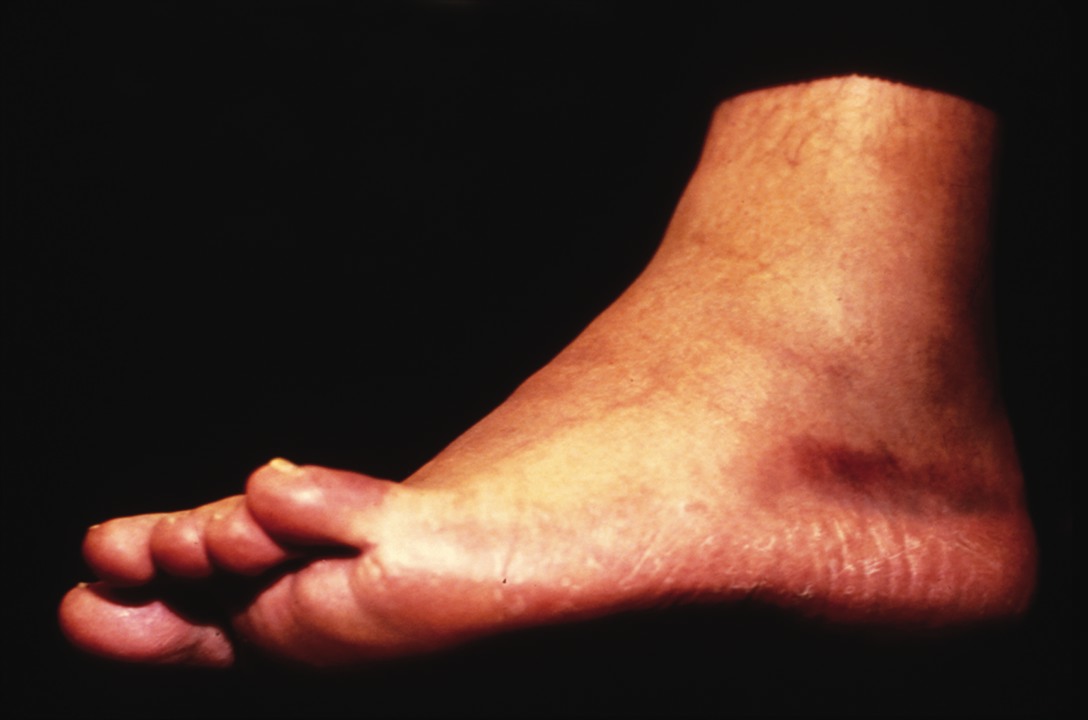

Study: MRI Can Change Ankle Pain Diagnosis

By Brian McCurdy, Senior Editor Can the use of magnetic resonance imaging (MRI) provide valuable insight into ankle injuries? A recent study in the American Journal of Roentgenology says MRI can potentially change diagnoses in patients with ankle injuries and possibly lead to less invasive treatments. Researchers studied 91 patients who were referred from one orthopedic foot and ankle surgeon for ankle MRI. The study concluded that MRI findings changed the management plans for 35 percent of patients in the study. For 32 percent of patients for whom management plans changed, practitioners formulated a less invasive plan, according to the study. The surgeon from whom patients were referred believed that in 66 percent of cases overall, the understanding of the patient’s condition had either depended on the MRI or had been improved by the imaging. Babak Baravarian, DPM, uses MRI studies “a great deal” when treating ankle pain. He says in cases of instability, there are frequent secondary findings like synovitis, osteochondral lesions or peroneal tendon injuries. “With good readings, a great deal of information is gained from an MRI study,” says Dr. Baravarian, the Co-Director of the Foot and Ankle Institute of Santa Monica. “I think the info is essential prior to most surgical cases about the ankle.” Lawrence A. DiDomenico, DPM says as costs decrease, it is easier to use the technology from an insurance standpoint. Increasing MRI use is becoming a more common and accepted practice pattern for musculoskeletal physicians. In the ‘80s, he recalls there was not much literature on specific soft tissue pathologies such as plantar fascia ruptures or peroneal tendon injuries. Dr. DiDomenico, an Adjunct Professor with the Ohio College of Podiatric Medicine, says MRI has made these conditions easier to diagnose, resulting in a recent increase in the reports in the literature. He adds that DPMs now see these pathologies more frequently. “It gives a much more accurate diagnosis and therefore, more focused treatment options for patients,” he says. Dr. DiDomenico says a facility without a well-trained musculoskeletal radiologist and/or MRI technologist may generate a poor reading (i.e., a one- or two-sentence report). Alternatively, more experienced staff will provide a detailed one- or two-page report, according to Dr. DiDomenico, the Director of the Reconstructive Rearfoot and Ankle Surgical Fellowship with the Ankle and Foot Care Centers in Youngstown, Ohio.